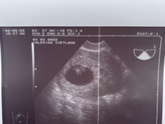

Первое узи

4 марта 2022 12:15

Вчера было первое узи. Все в порядке!

Сердцебиение послушать не дали, но врач показала мне на мониторе, как бьется маленькое сердечко. Так трогательно, что я расплакалась.